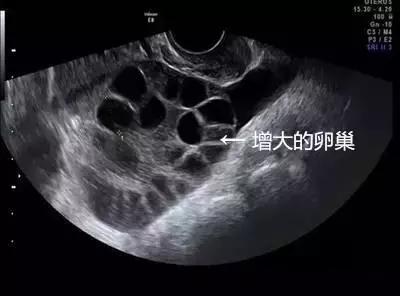

取卵成功后,中介就没有再联系琳琳。但取卵5天后,琳琳出现持续性下腹胀,还有十分明显的胸闷症状。她再次联系卖卵中介,但对方拒绝承担责任,还威胁琳琳不要再纠缠。琳琳到这家妇幼保健院就诊,B超提示腹腔内大量积液,胸腔少量积液,卵巢增大超过3倍以上,考虑是卵巢过度刺激综合症,被收治住院。